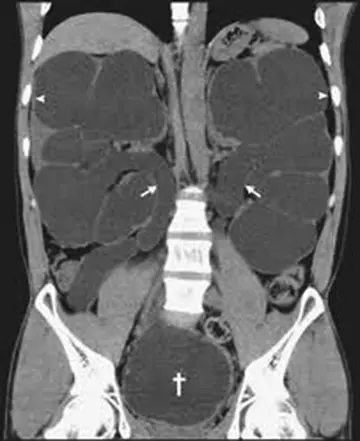

هیدرونفروز و پلی‌سیتمی

یک مرد 34 ساله‌ی غیرسیگاری برای ارزیابی سابقه‌ی 3 ساله‌ی پلی‌سیتمی و نیاز به فلبوتومی ماهانه ارجاع شد. سابقه‌ی طبی بیمار ازنظر دیابت بی‌مزه‌ی نفروژنیک مادرزادی با بازده‌ی تقریبی‌12‌تا‌15‌لیتر ادرار درروز قابل‌توجه بود.